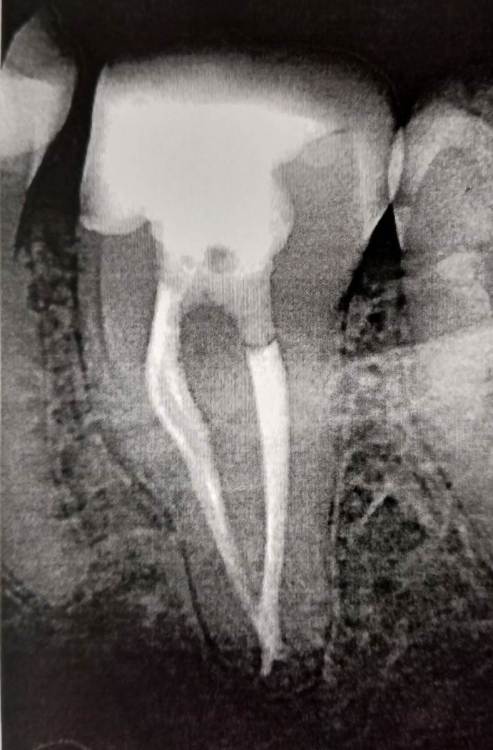

Ico Опубликовано 21 февраля, 2022 Автор Поделиться Опубликовано 21 февраля, 2022 Основная сложность это последовательность в обтурации.Сначала были обтурирован сплит (2 мелких вестибулярных),в язычном оставлен бумажный пин,т.к места не было для трех штифтов.После удаления излишков обтурировал и его.Самое сложное для меня это удаление излишков и плохая видимость.Буду признателен советам,кто и как такие пакует. 3 2 1 Ссылка на комментарий

Ico Опубликовано 19 марта, 2022 Автор Поделиться Опубликовано 19 марта, 2022 Микродоступ того не стоит,есть адекватный доступ для адекватного и без рисков эндо.В данном случае мартенситных еще тогда не было,столкнулся с проблемами в виде ступеней,паковкой,потратил больше времени чем хотел,2 визита по 2 часа.Диагноз - хронический пульпит в обострении.Материалы - пре реисы и патфаилы,ковер до 15к,упор на 25к.Паковка волна. 3 1 Ссылка на комментарий